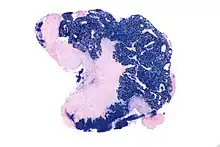

| Micrograph showing a nasopharyngeal carcinoma positive for Epstein-Barr virus-encoded small RNAs (EBER). | |

Nasopharyngeal carcinoma (NPC), or nasopharynx cancer, is the most common cancer originating in the nasopharynx, most commonly in the postero-lateral nasopharynx or pharyngeal recess (fossa of Rosenmüller), accounting for 50% of cases. NPC occurs in children and adults. NPC differs significantly from other cancers of the head and neck in its occurrence, causes, clinical behavior, and treatment. It is vastly more common in certain regions of East Asia and Africa than elsewhere, with viral, dietary and genetic factors implicated in its causation.[1] It is most common in males. It is a squamous cell carcinoma of an undifferentiated type. Squamous epithelial cells are a flat type of cell found in the skin and the membranes that line some body cavities. Undifferentiated cells are cells that do not have their mature features or functions.

NPC is caused by a combination of factors: viral, environmental influences, and heredity.[4] The viral influence is associated with infection with Epstein–Barr virus (EBV).[5][6] The Epstein-Barr virus is one of the most common viruses. 95% of all people in the U.S. are exposed to this virus by the time they are 30–40 years old. The World Health Organization does not have set preventative measures for this virus because it is so easily spread and is worldwide. Very rarely does Epstein-Barr virus lead to cancer, which suggests a variety of influencing factors. Other likely causes include genetic susceptibility and consumption of food (in particular salted fish)[7] containing carcinogenic volatile nitrosamines.[8] Various mutations that activate NF-κB signalling have been reported in almost half of NPC cases investigated.[9]

The association between Epstein-Barr virus and nasopharyngeal carcinoma is unequivocal in World Health Organization (WHO) types II and III tumors but less well-established for WHO type I (WHO-I) NPC, where preliminary evaluation has suggested that human papillomavirus (HPV) may be associated.[10] EBV DNA was detectable in the blood plasma samples of 96% of patients with non-keratinizing NPC, compared with only 7% in controls.[6] The detection of nuclear antigen associated with Epstein-Barr virus (EBNA) and viral DNA in NPC type 2 and 3, has revealed that EBV can infect epithelial cells and is associated with their transformation. The cause of NPC (particularly the endemic form) seems to follow a multi-step process, in which EBV, ethnic background, and environmental carcinogens all seem to play an important role. More importantly, EBV DNA levels appear to correlate with treatment response and may predict disease recurrence, suggesting that they may be an independent indicator of prognosis. The mechanism by which EBV alters nasopharyngeal cells is being elucidated[11] to provide a rational therapeutic target.[11]